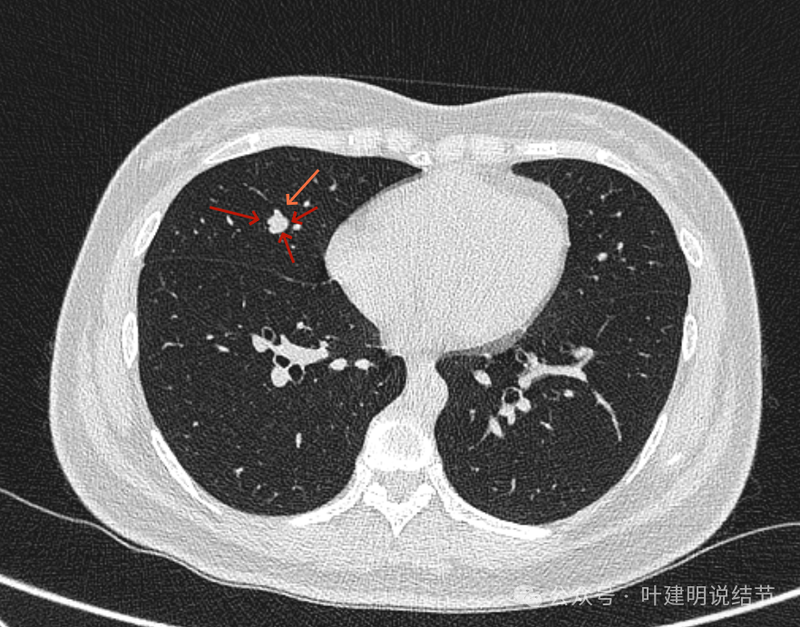

再看矢状位影像:

桔色的是血管,红色的是病灶,两者之间有间隙仍用天蓝色细线标注。

紧挨但仍有缝隙的。

血管贴着病灶,病灶表面略有毛糙之处。

血管有形成轻微血管弯征,两者紧贴。

两支血管夹着病灶,密度不同,有低密度间隙。

病灶与两侧血管关系均密切,明显觉得密度是不一样的,血管的密度略高,结节的略低。

病赤与血管在蓝色箭头处失去间隙,像是侵蚀血管壁,造成血管受侵犯破坏。病灶是软组织密度的,而且整体看有膨胀感。

病灶密度稍不均。表面不光滑。

病灶与边上血管间隙不清。

桔色箭头所示的血管受压稍有移位。

密度不同,关系密切。

边缘区域也是有膨胀感。

血管与病灶脱开后的样子。

边缘区也是基本上实性的。